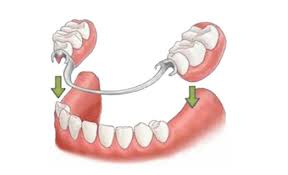

5. Prótesis mal adaptadas: tanto en prótesis completas y prótesis fijas como coronas dentales. Si no tienen buena adaptación acumulan muchos restos y bacterias que inevitablemente generan un olor insoportable. Recuerden que deben lavar las prótesis removibles constantemente como si fueran sus dientes.